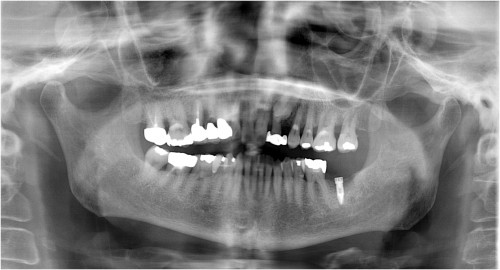

同パノラマ写真